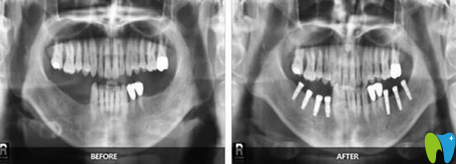

【牙齒種植】:

顧客評(píng)價(jià):爸爸在這里做的即刻種植,技術(shù)挺不錯(cuò)的,種植完牙齒當(dāng)天就能吃飯,剛開(kāi)始我還擔(dān)心老年人不好,沒(méi)想到也挺不錯(cuò)的,而且老爸現(xiàn)在胃口挺好的,胃口好了心情也不錯(cuò),挺適合老年人的。

福州貝臣齒科種植牙